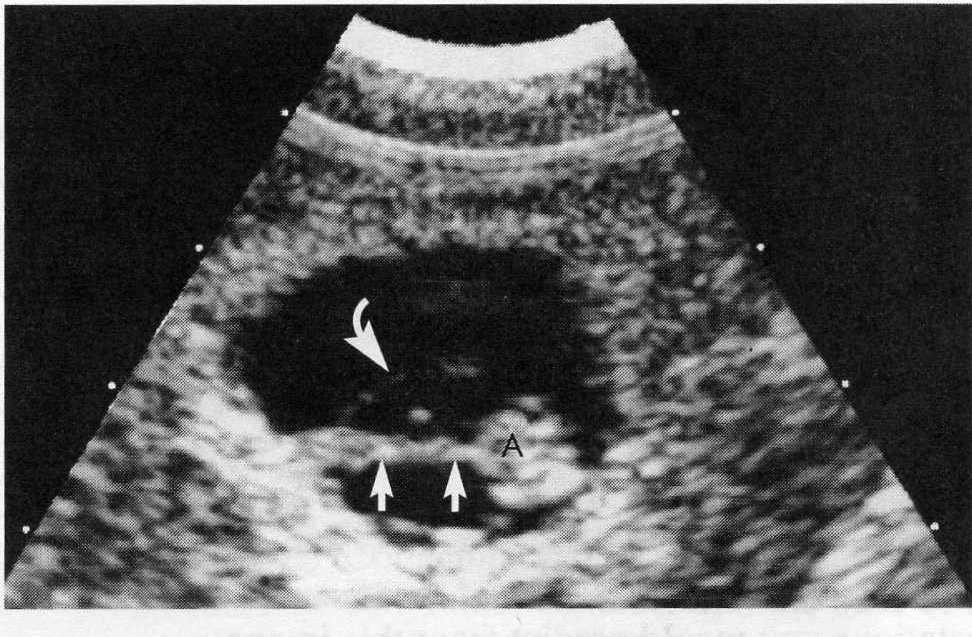

in this 8 week gestation name the structure taht the curved arrow is pointing too.

name the structure that the straight arrows are pointing too

amniotic membrane

umbilical cord